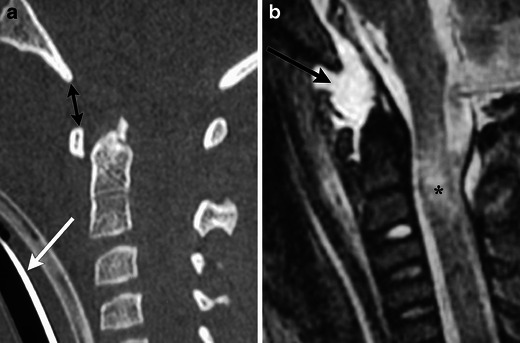

Fig. 12.

Flexion teardrop fracture. (a) Sagittal MDCT image demonstrates fractures of the anteroinferior corner of C5 (black arrow) and horizontally directed fracture through the posterior elements (white arrow), with resultant focal kyphosis and loss of vertebral body height. (b) Sagittal STIR image in another patient shows high signal from the fracture (white arrow), within the disrupted interspinous ligaments (black asterisk), and associated cord contusion (black arrow). There is also severe narrowing of the spinal canal